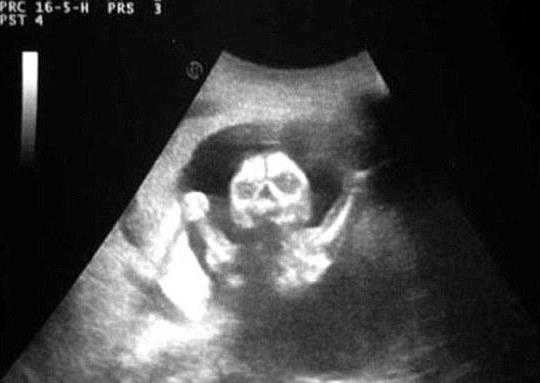

图中的宝宝影像像一只恶魔,长着黑色的大眼睛,嘴巴张的很大,来势汹汹。